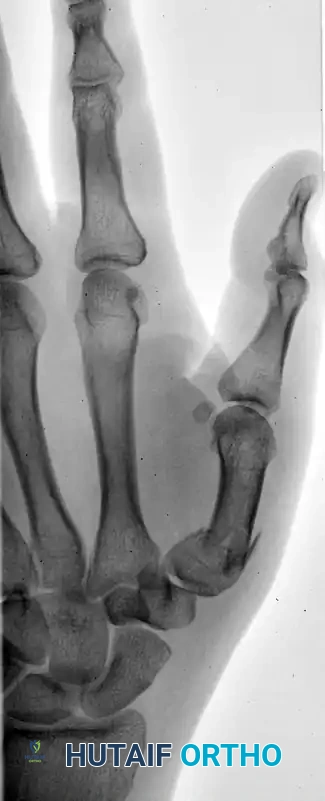

The following sequence illustrates the progression from injury to successful closed reduction and K-wire fixation into the trapezium: